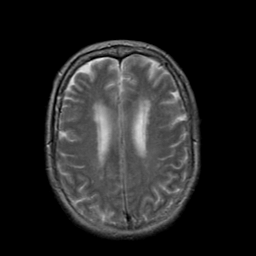

Stroke:T2-weighted MR #2 -- Slice #17

[Home][Help][Clinical] Slice 17